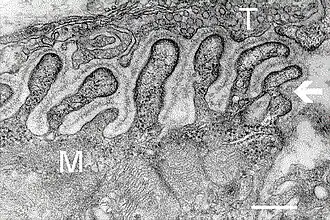

Нервно-мышечный синапс

2. Сарколемма

3. Синаптический пузырек

4. Никотиновый ацетилхолиновый рецептор

5. Митохондрия

В нервно-мышечной системе нервы центральной нервной системы и периферической нервной системы связаны и работают вместе с мышцами[1]. Нервный отросток подходя к сарколемме мышечного волокна утрачивает миелиновую оболочку и образует сложный аппарат с плазматической мембраной мышечного волокна, образующийся из выпячиваний аксона и цитолеммы мышечного волокна, создавая глубокие «карманы». Синаптическая мембрана аксона и постсинаптическая мембрана мышечного волокна разделены синаптической щелью. В этой области мышечное волокно не имеет поперечной исчерченности, характерно скопление митохондрий и ядер. Терминали аксонов содержат большое количество митохондрий и синаптических пузырьков с медиатором ацетилхолином.